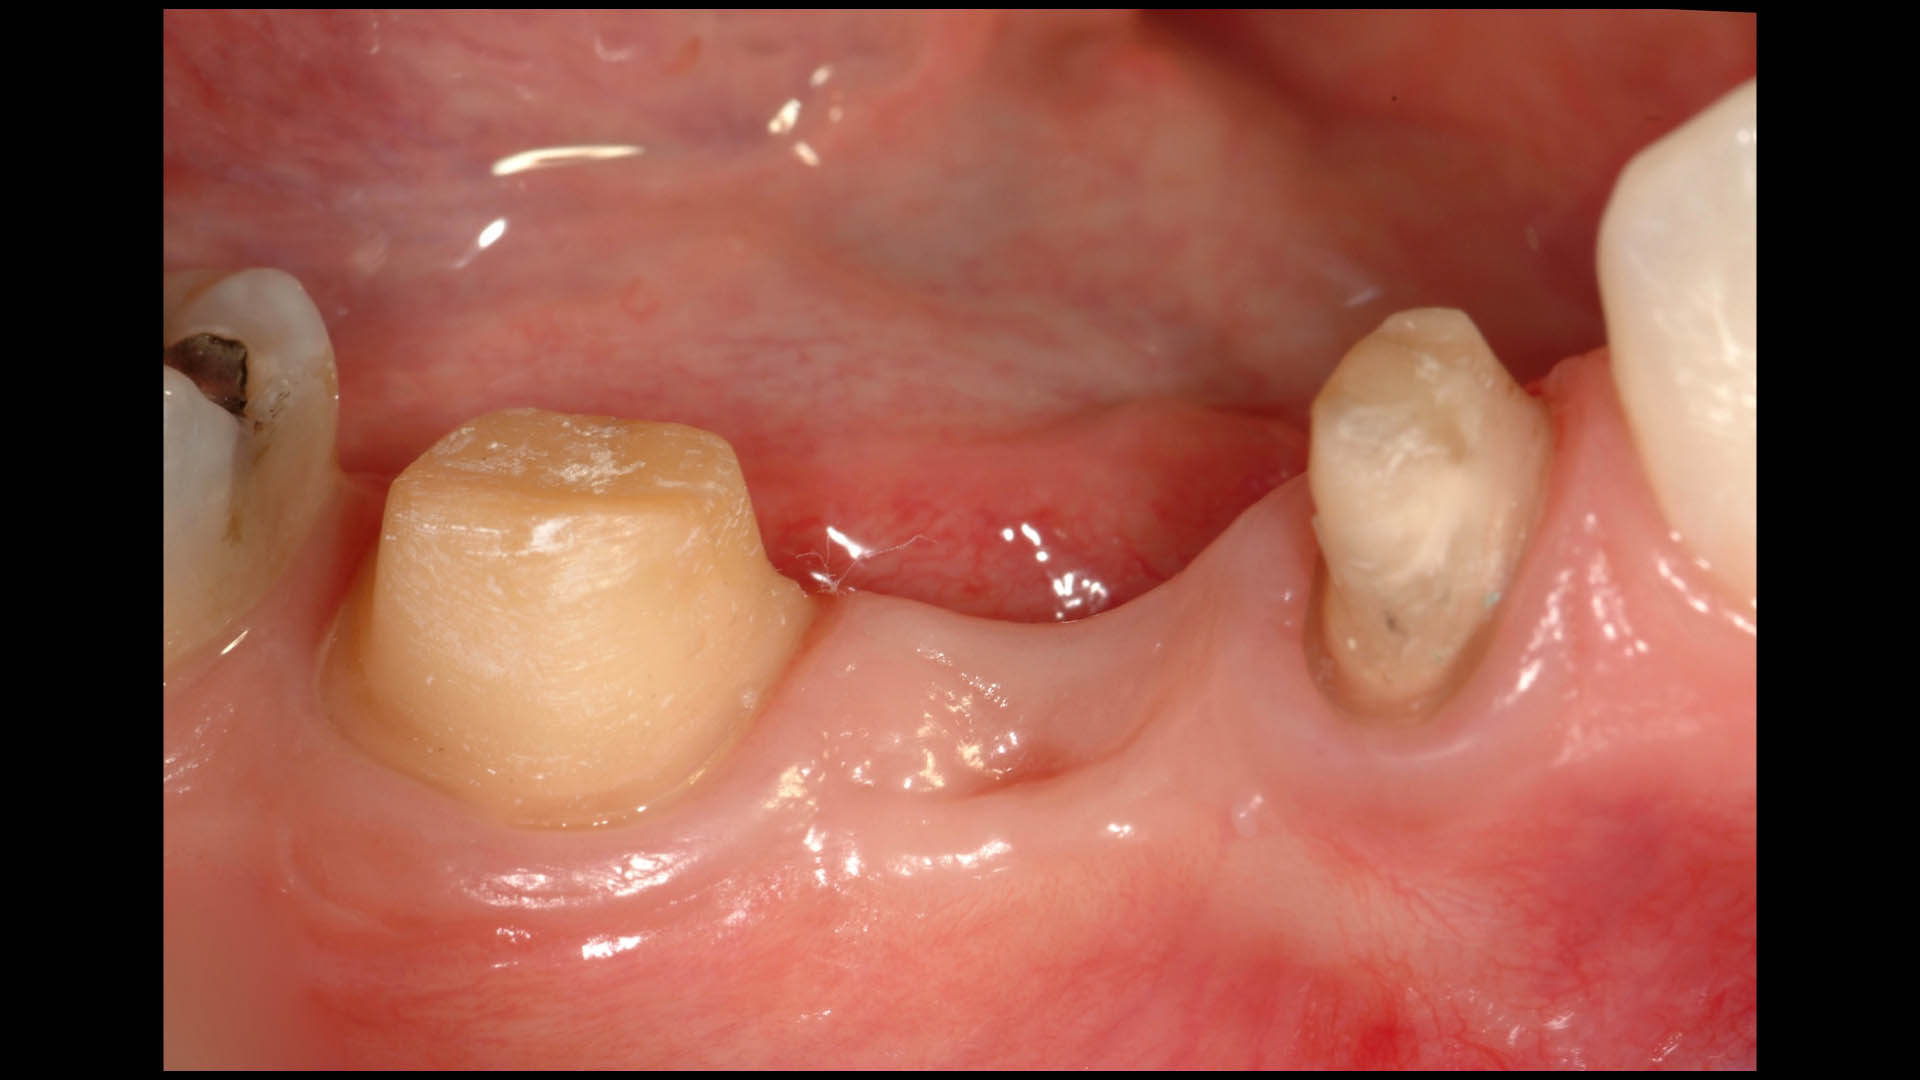

Take a glimpse into the magic of Coral Gables Dentistry through our before and after pictures. See firsthand the incredible smile makeover transformations that have brought confidence and joy to our patients.